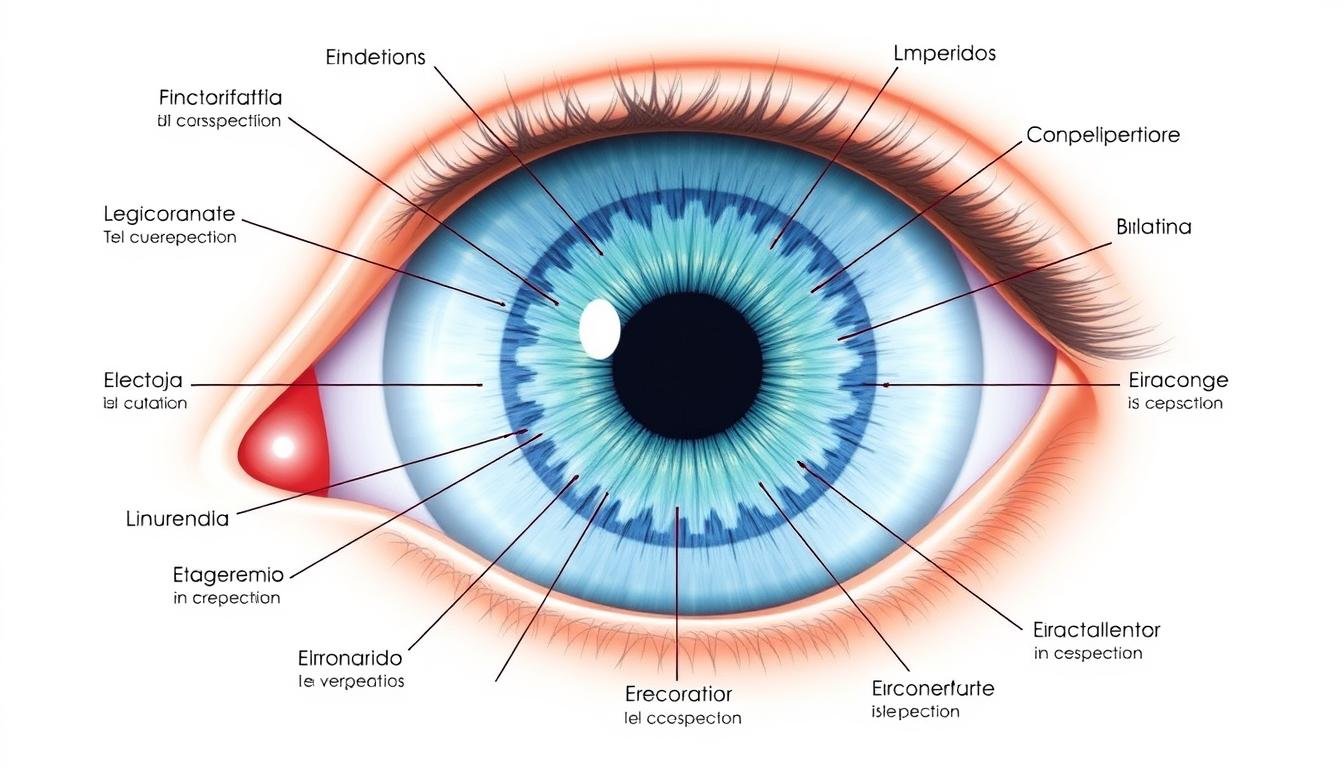

Mapa de correspondencias del iris con los órganos del cuerpo humano

Según los practicantes de la lectura del iris, cada zona del iris corresponde a una parte específica del cuerpo. Por ejemplo, el área cercana a la pupila se relaciona con el sistema digestivo, mientras que las zonas más externas corresponden a la piel, articulaciones y sistema linfático. Los cambios en la textura, color o la aparición de marcas en estas zonas pueden indicar desequilibrios o predisposiciones a ciertas condiciones de salud.

- Mapeo por zonas: Utilizando un mapa de referencia del iris, el profesional analiza diferentes zonas que corresponden a órganos y sistemas específicos. Por ejemplo, el área cercana a la pupila se relaciona con el sistema digestivo, mientras que las zonas más externas corresponden a la piel y el sistema linfático.

- Identificación de signos y marcas: Se analizan signos específicos como lagunas (áreas oscuras), radios solares (líneas que irradian desde la pupila), anillos de tensión (círculos concéntricos) y otros marcadores que pueden indicar estados particulares de los tejidos.